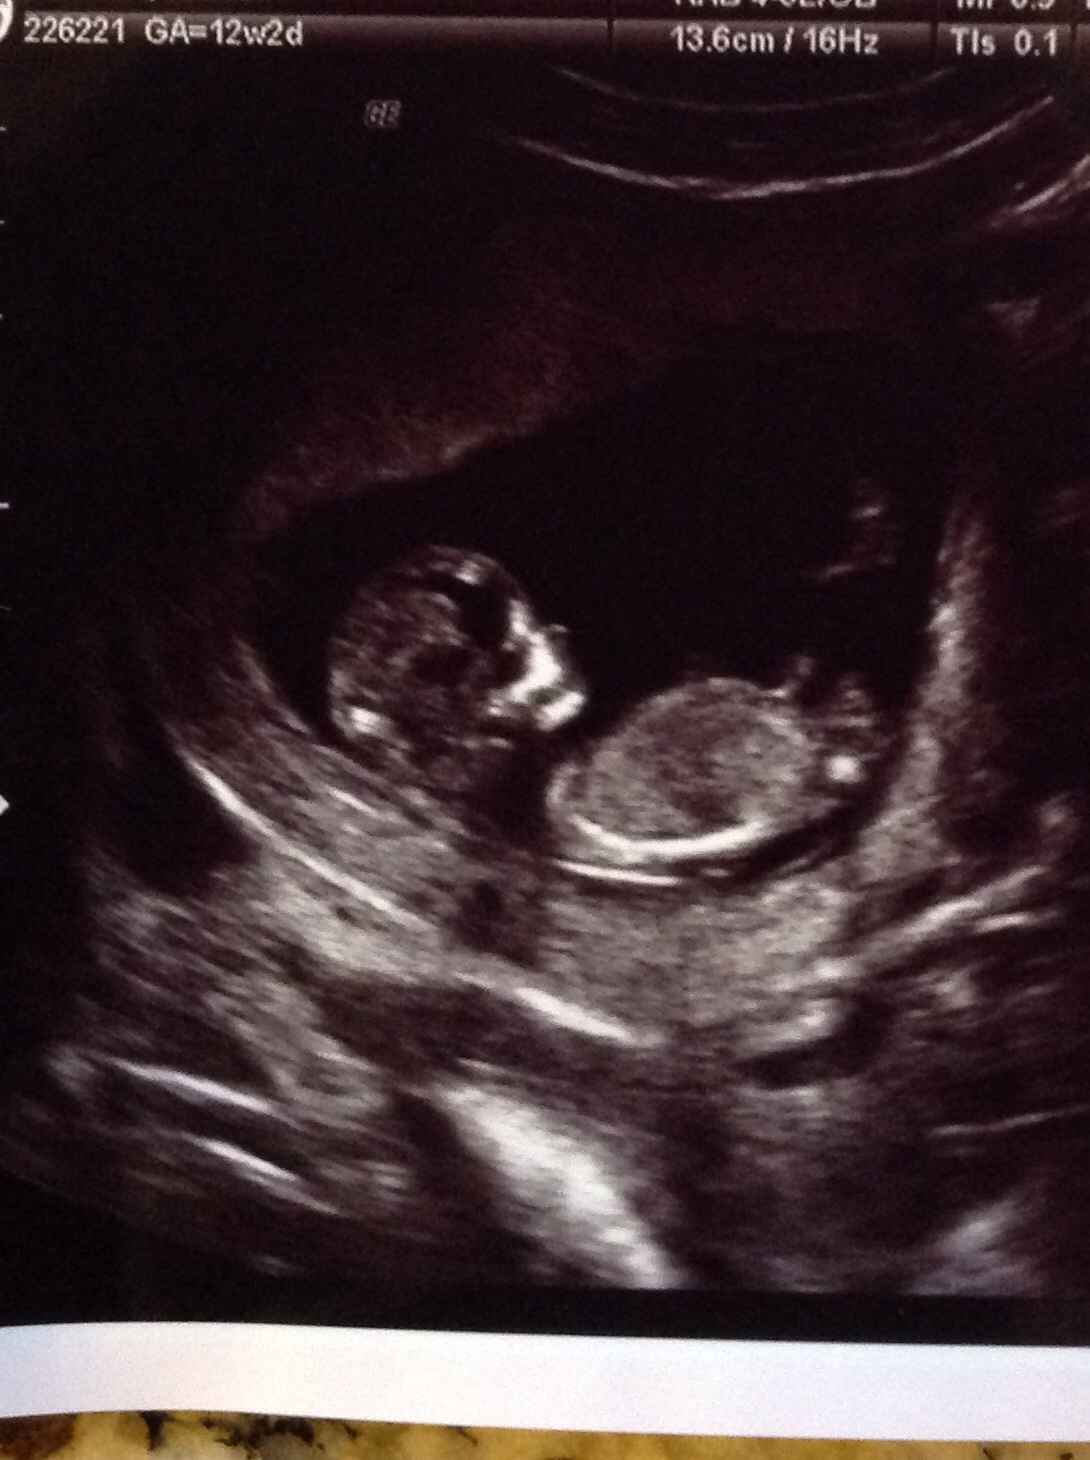

Girl

Yay-I like that answer! I have 2 fabulous boys already so a girl would be great!

maybe girl

lean girl :-)

I think girl

Possibly a boy from the 2nd pic. I'm not seeing a nub in the others.

I'm leaning girl but the pics are very in clear for the nub